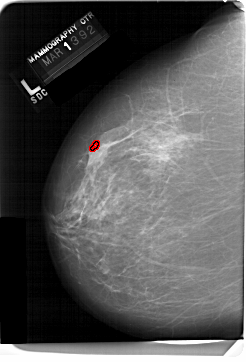

A_1466_1.RIGHT_CC

RIGHT_MLO LINES 6871 PIXELS_PER_LINE 4951 BITS_PER_PIXEL 12 RESOLUTION 43.5 NON_OVERLAY

FILE: A_1466_1.LEFT_MLO.OVERLAY

TOTAL_ABNORMALITIES 1

ABNORMALITY 1

LESION_TYPE CALCIFICATION TYPE PLEOMORPHIC DISTRIBUTION CLUSTERED

ASSESSMENT 4

SUBTLETY 2

PATHOLOGY MALIGNANT

TOTAL_OUTLINES 1

BOUNDARY